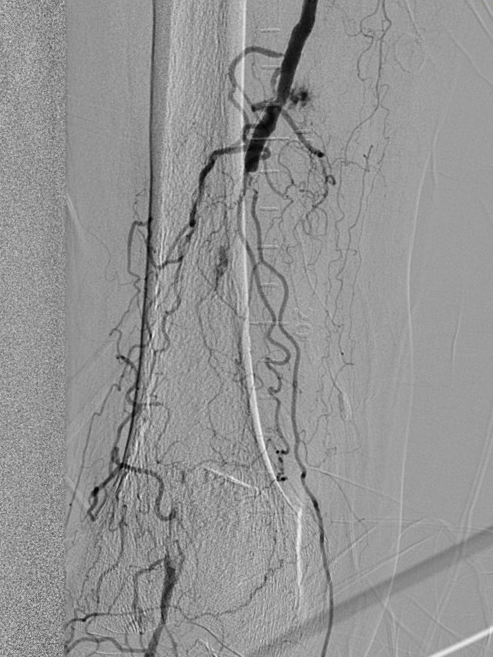

图3

膝关节下血管闭塞

图3为术前DSA,图4为术后DSA